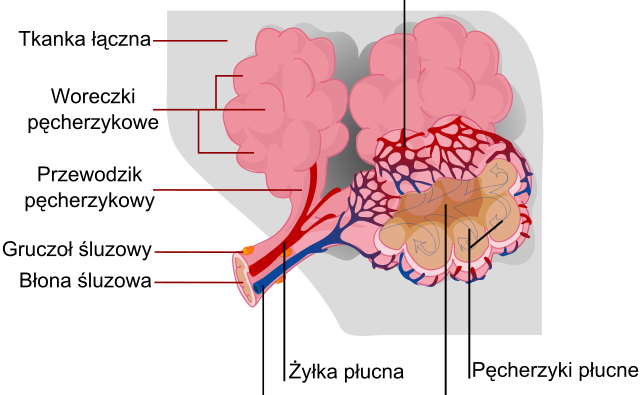

Vejpanje in drugi podobni načini inhalacij so v zadnjem desetletju vse bolj popularni, tudi ker se tržijo kot manj škodljiva alternativa kajenju industrijsko predelanega tobaka in marihuane. Znanstvena ekipa je preiskala vpliv dveh redčil v tekočinah za elektronske cigarete – vitamina E in tokoferol acetata – na fiziološko neoporečnost membrane v pljučnem mešičku. Ugotovitve je predstavila v reviji Langmuir.

Leta 2019 je ameriški Center za nadzor in preprečevanje bolezni ob velikem porastu pljučnih poškodb pri intenzivnih uporabnikih e-cigaret in vejpov prvič izdal opozorilo glede njihove prekomerne uporabe. Vitamin E in njegov derivat, tokoferol acetat, sta bila v študijah, ki so sledile, pri uporabnicah prepoznana kot potencialna krivca za poškodbe pljučnega tkiva. Kljub temu da ju regulatorni organi prepoznavajo kot varna v živilskih izdelkih, izpostavljajo dva problematična vidika uporabe v tekočini za vejpe. Zaradi kopičenja v membrani naj bi motila delovanje pljučnih mešičkov. Poleg tega se ob uparjanju pri visokih temperaturah tvorijo dodatni produkti, ki jih v živilstvu ne pričakujemo, posledično pa tudi ne vrednotimo njihove varnosti.

Znanstvena ekipa je želela preveriti, na kakšen način postopno nalaganje vitamina E in njegovega acetatnega derivata v pljučnih mešičkih vpliva na njihovo fiziološko funkcionalnost. Obe molekuli in nekateri produkti, ki nastanejo med uparjanjem tekočine za vejpe, se namreč usidrajo v tanko plast površinsko aktivnih molekul v mešičkih. Te skrbijo, da membrane mešičkov vzdržujejo napeto, kroglasto obliko in da je izmenjava plinov optimalna. Porušena površinska napetost lahko po drugi strani vodi v vnetje pljučnega tkiva, slabšo predihanost pljuč in škodljiv upad izmenjave plinov v mešičkih.

Poskuse so izvajali na modelni membrani s tanko plastjo surfaktantov. Glavna naloga surfaktantov je stabilizacija površine mešička ne glede na tlak plina, ki se med vdihanjem in izdihanjem spreminja. V študiji so preverjali spremembe v mehanskih lastnostih membrane in tudi strukturno organizacijo molekul na njeni površini glede na različne deleže tokoferola in njegovega acetatnega derivata v tekočini za vejpe. Z naborom mikroskopskih opazovanj in fizikalnih meritev na površini membrane s surfaktantom so ugotovili, da njuno nalaganje zmanjša stabilnost membrane. Nestabilnost izhaja iz povečane fluidnosti membranskih surfaktantov in spremenjene geometrije membrane.